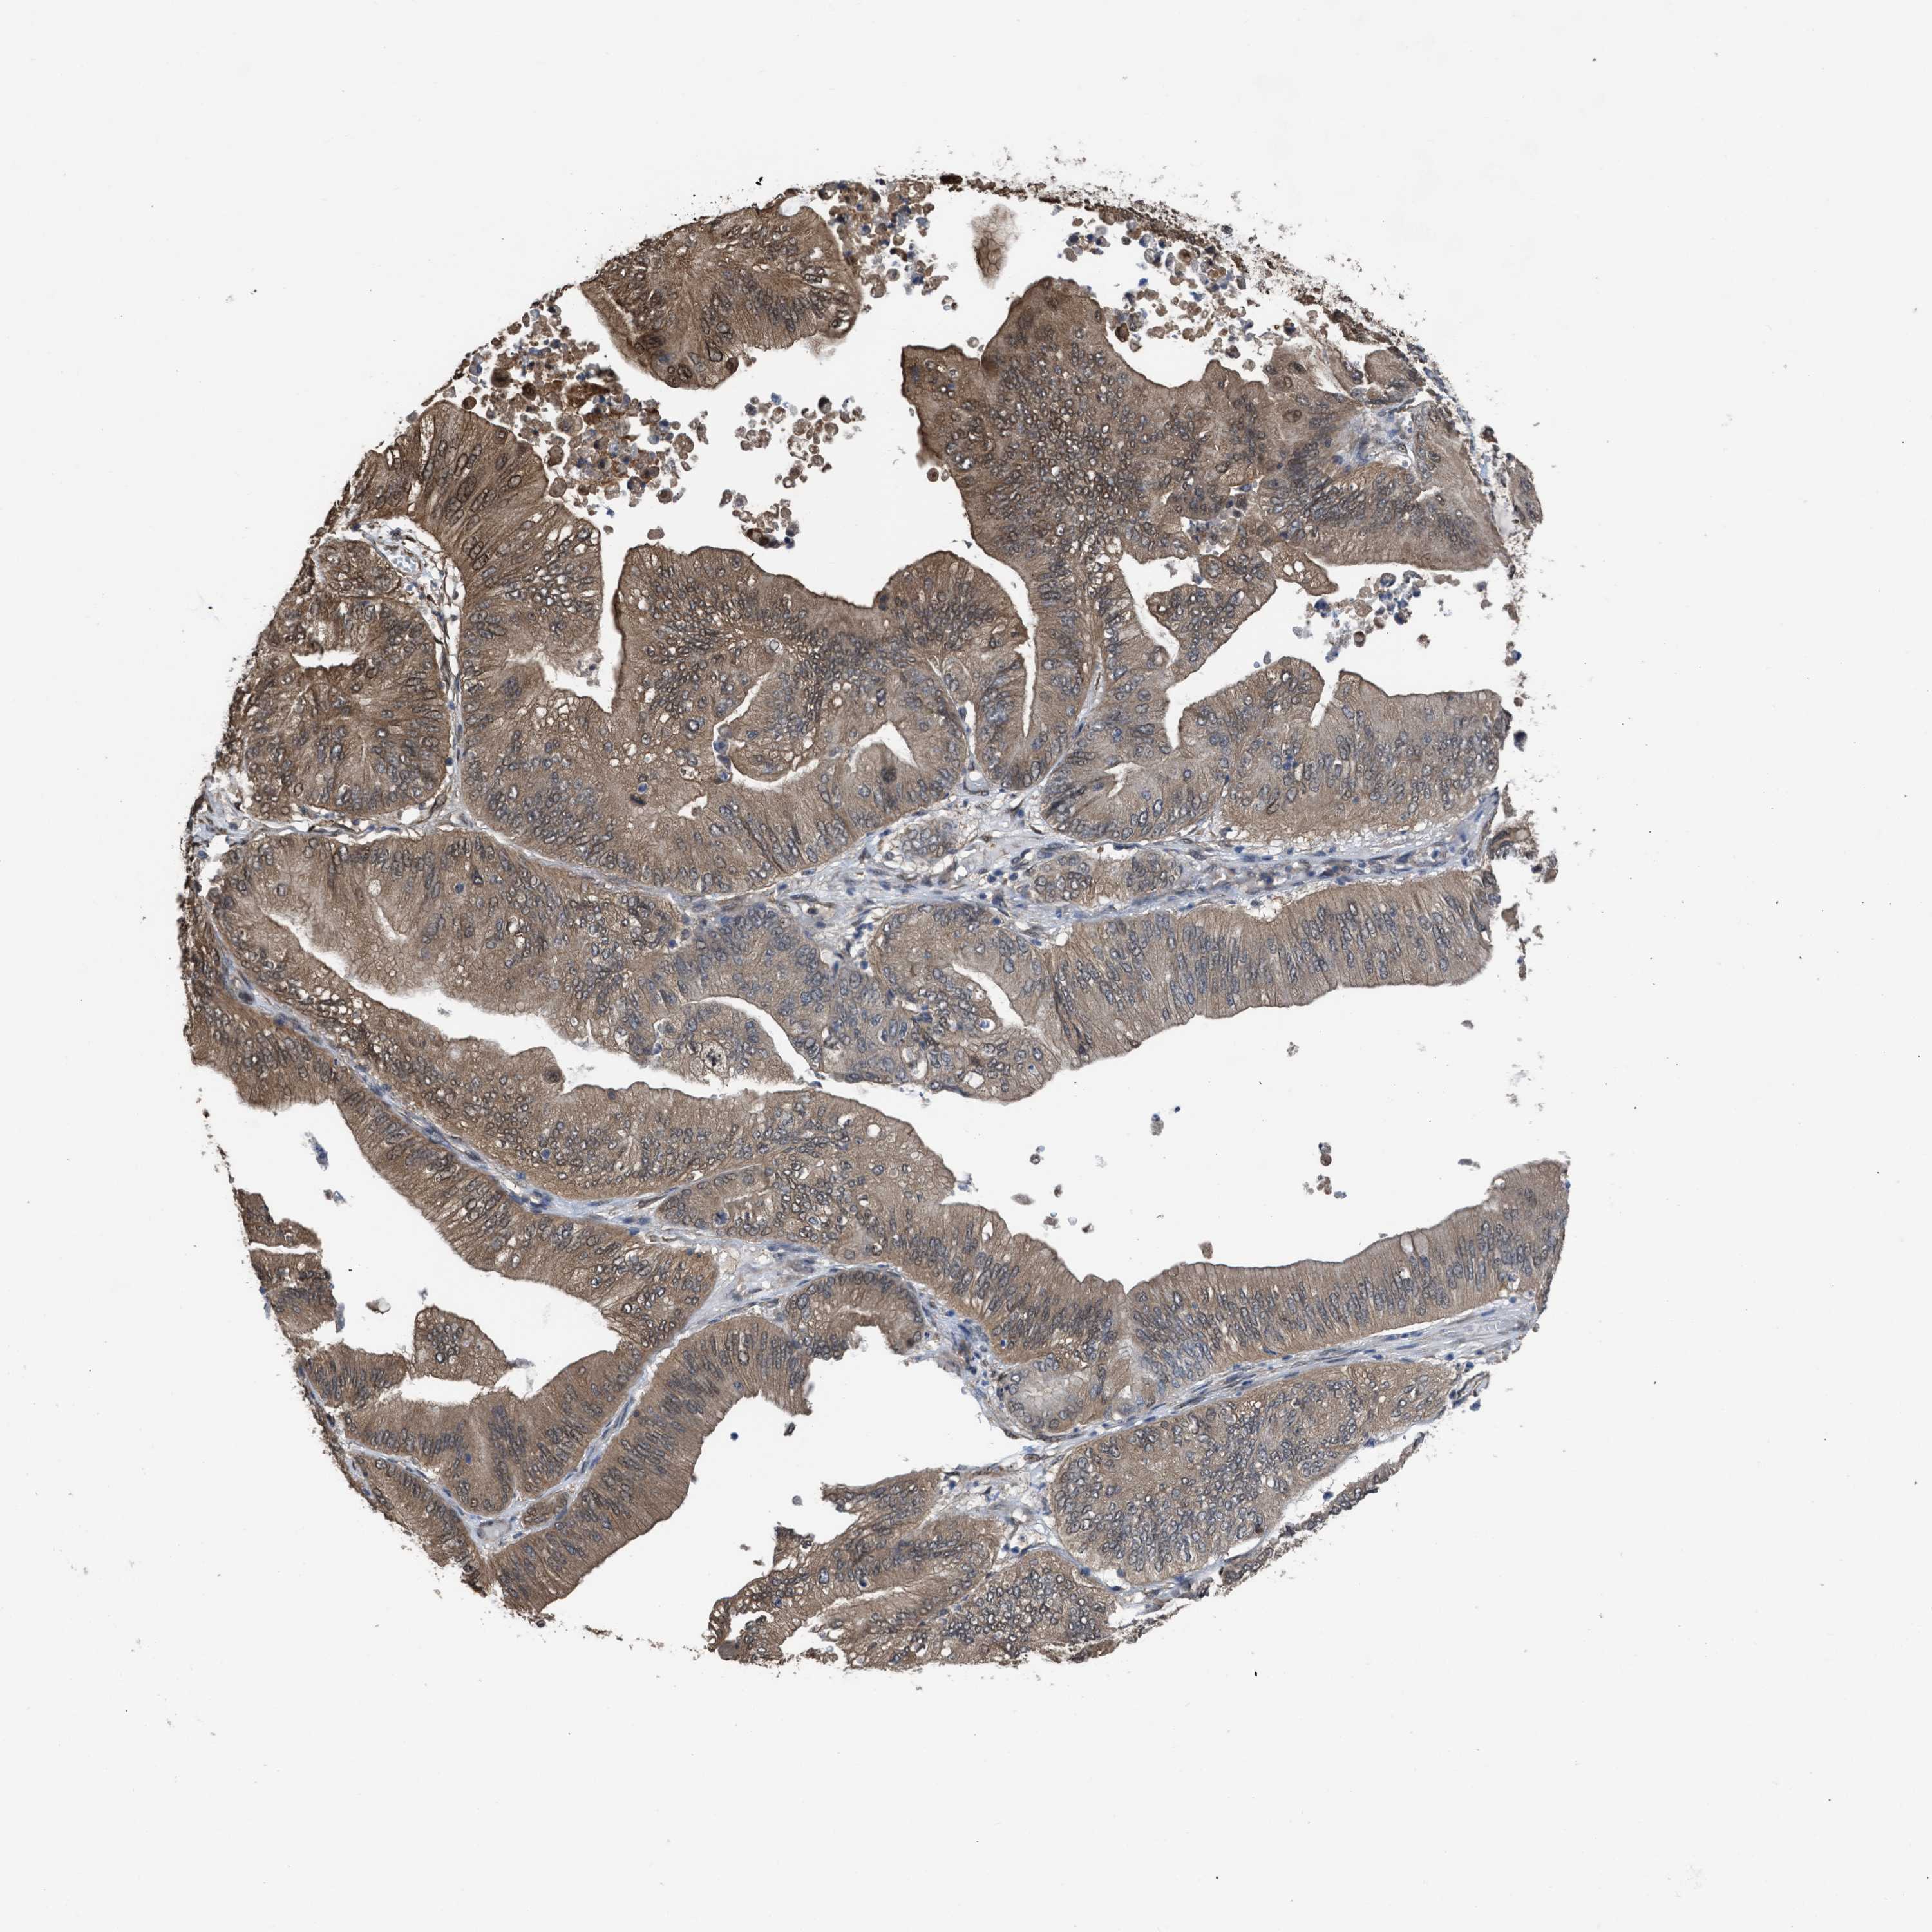

OVARIAN CANCER - Protein expressioni

A mouse-over function shows sample information and annotation data. Click on an image to view it in a full screen mode. Samples can be filtered based on level of antibody staining by selecting one or several of the following categories: high, medium, low and not detected. The assay and annotation is described here.

Note that samples used for immunohistochemistry by the Human Protein Atlas do not correspond to samples in the TCGA dataset.

Antibody stainingi

Antibody staining in the annotated cell types in the current human tissue is reported as not detected, low, medium, or high, based on conventional immunohistochemistry profiling in selected tissues. This score is based on the combination of the staining intensity and fraction of stained cells.

Each image is clickable and will lead to virtual microscopy that enables deeper exploration of all samples and also displays staining intensity scores, fraction scores and subcellular localization as well as patient and tissue information for each sample.

Antibody HPA026918

Antibody CAB013274

Antibody CAB018389

Cystadenocarcinoma, serous, NOS

Carcinoma, endometroid

Cystadenocarcinoma, mucinous, NOS

Carcinoma, NOS